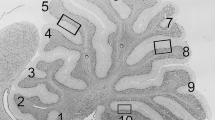

Npc1 nmf164 mice display a reduced density of GNs in the external granule layer (EGL), which is due to reduced proliferation of GN precursors. A Representative sections are shown in the figure. Higher magnification fields of EGL base or crown of lobules II and X on the right of low magnification fields show that the EGL of PN15 Npc1 nmf164 mice is thinner than that of age-matched wt mice. Scale bar indicate 250 μm (panels) and 50 μm (insets). B Histograms represent GN densities (mean ± SEM of all sections examined; N = 4 mice/genotype; 3–4 sections/mouse) determined in 100 μm2 regions of the crowns of wt and Npc1 nmf164 mice anterior (I-V) and posterior (VI-X) lobules. C A representative field showing BrdU-positive cells (red) of fissure between lobules II and III of PN13 wt and Npc1 nmf164 mice. Scale bar indicates 50 μm. D Histograms represent the number of BrdU-positive cells (mean ± SEM; 4 mice/genotype; 3–4 sections/mouse) determined in 100 μm2 regions corresponding to the bases and crowns of PN13 and PN15 wt and Npc1 nmf164 mice anterior (I–V) and posterior (VI–X) lobules. Asterisks indicate statistically significant differences (unpaired two-tailed Student’s t test, ** p < 0.001; *** p < 0.0001). (PDF 1513 kb)